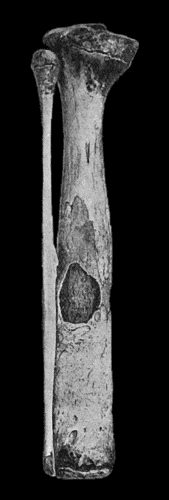

118.Shaft of the Femur after Acute Osteomyelitis 444

119.Femur and Tibia showing results of Acute Osteomyelitis 445